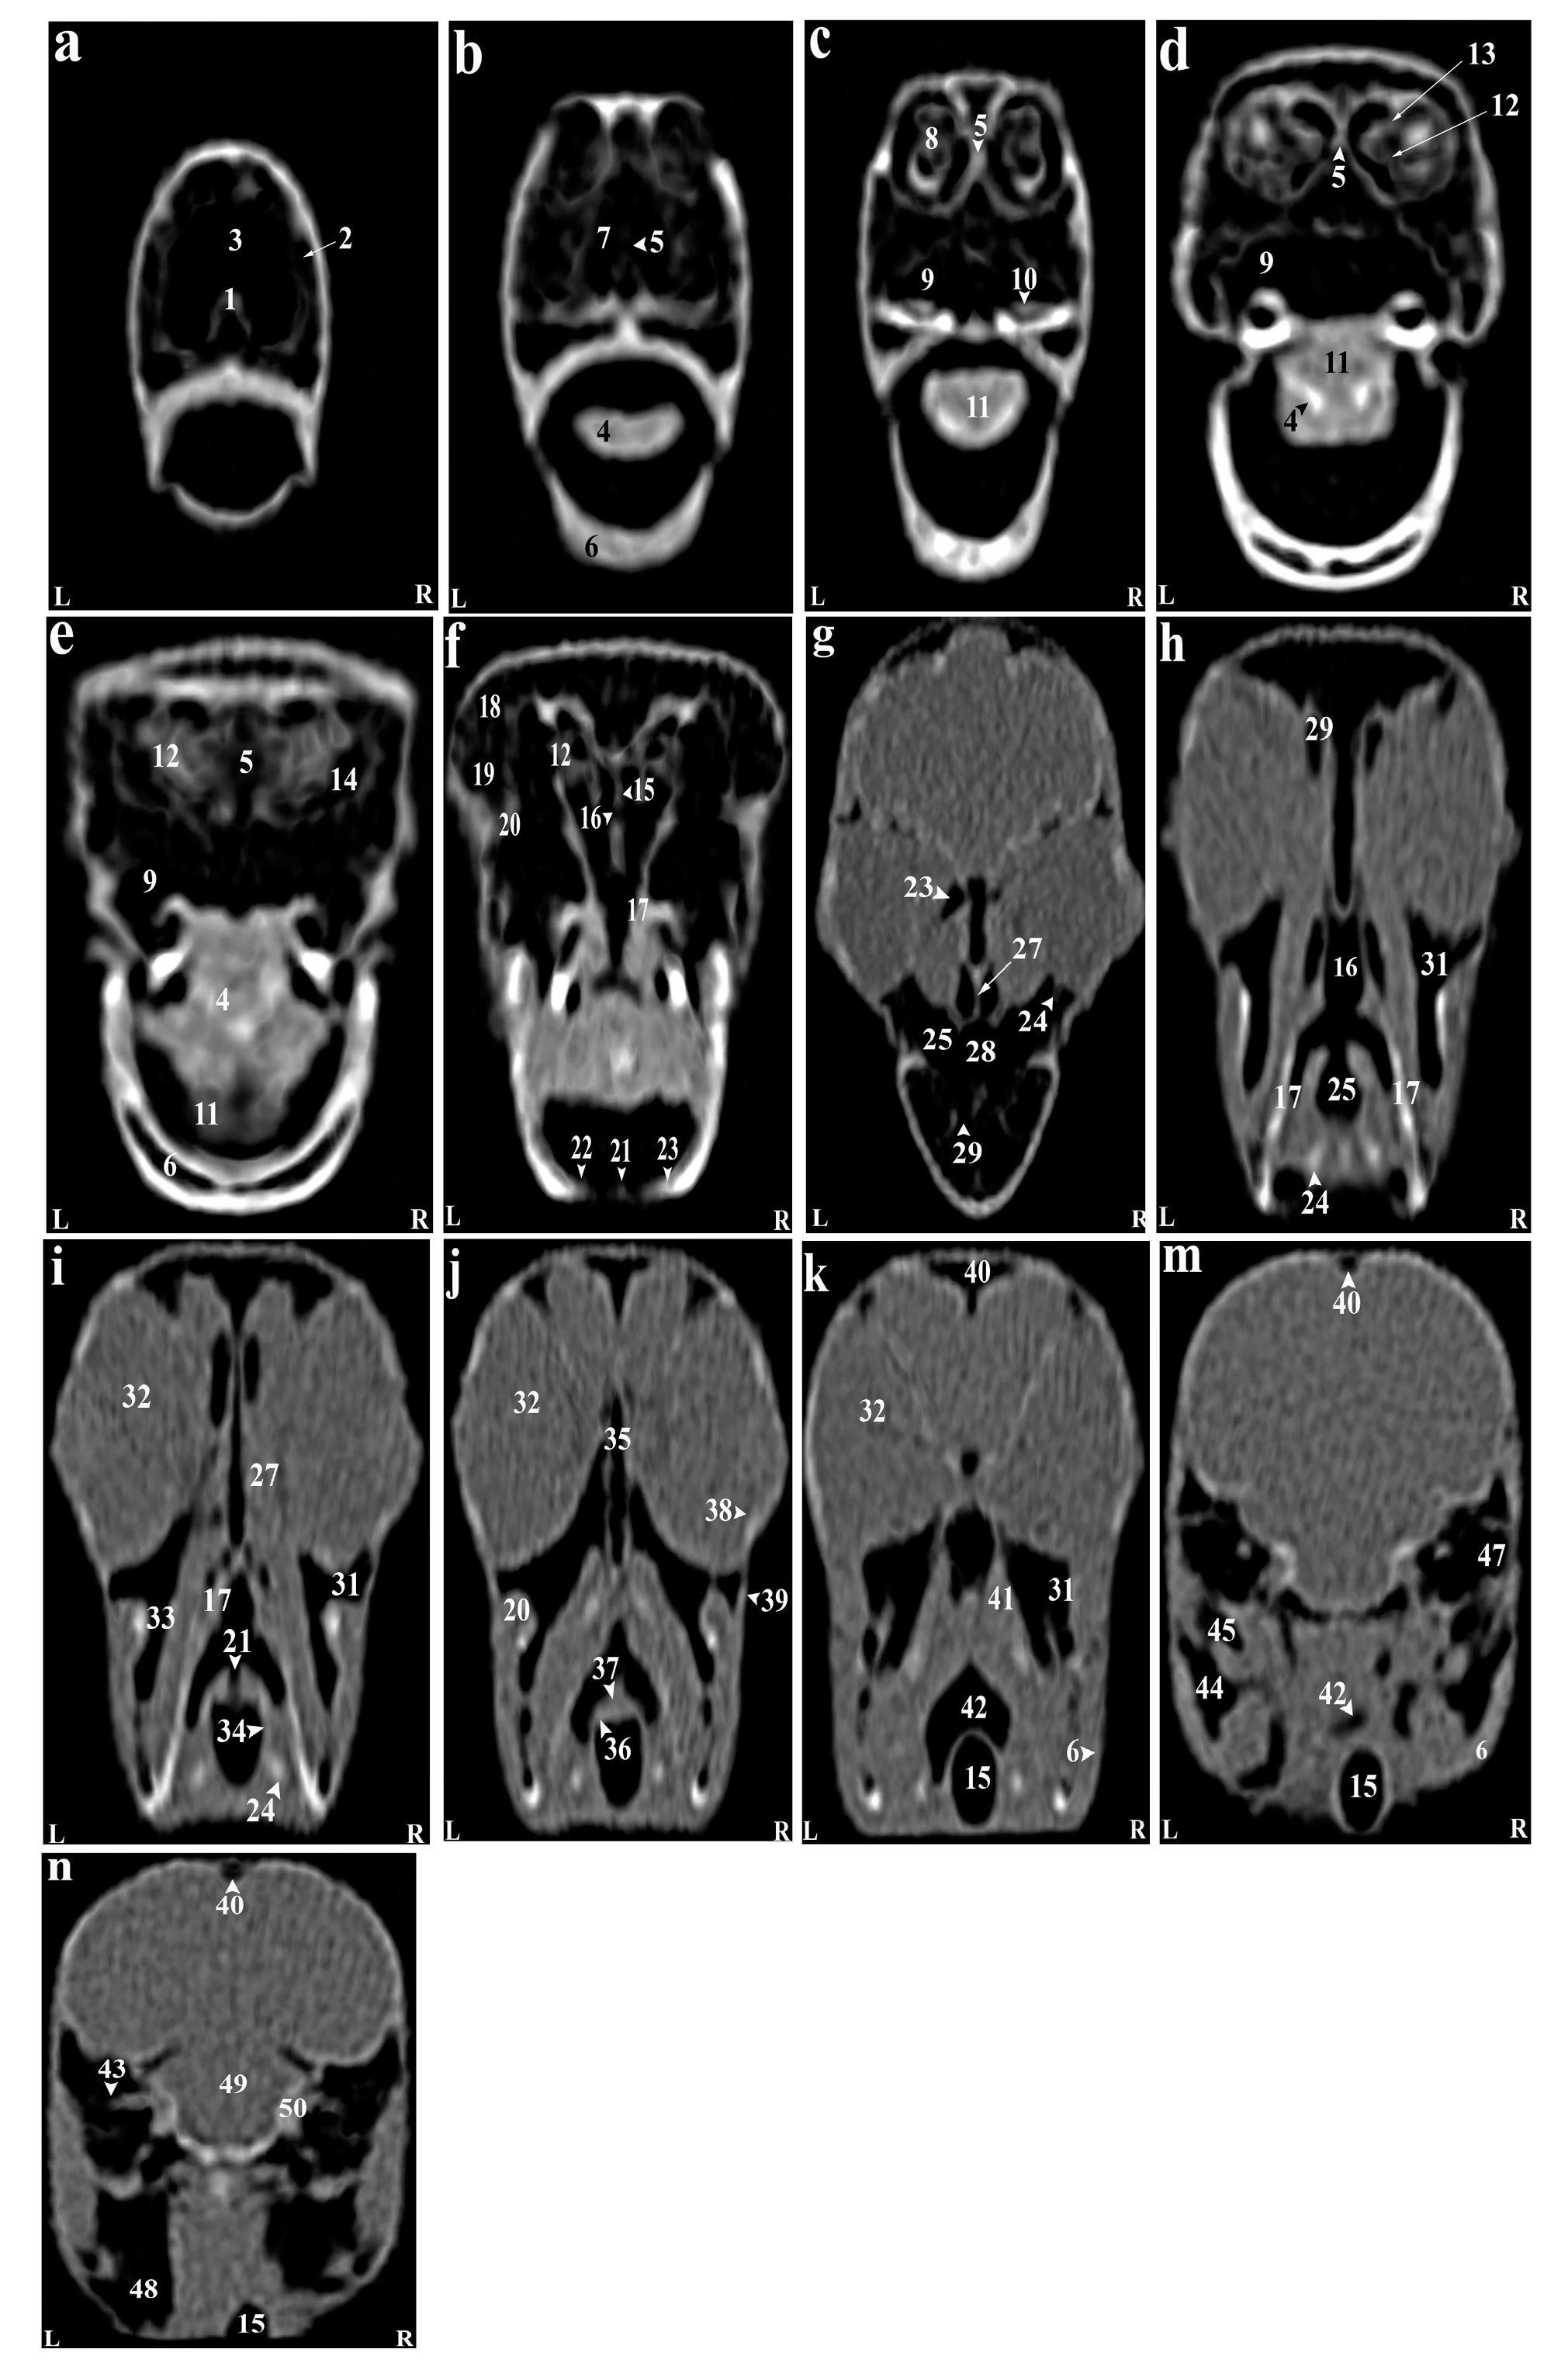

Reconstructed CT images revealed that most structures of the head of the Rose-ringed parakeet (Psittacula krameri) were identifiable. In the 3D images, the parrot's head appeared rounded and compact. The jugal arch and the palatine bone were fused in the remaining parts of the skull, except for the cranial facial bones. Even small bones of the head, such as ear bones and entoglossal bones inside the mouth, could also be evaluated in these CT images. Using the lung window filter, it was possible to observe the bony trabecular in the head. This setting also enabled evaluation of the parietal and temporal bones, nasal conchae, epithelial membranes, the external ear canal, and bony labyrinth. Further, with covering tissues, different parts of the infraorbital sinus could be observed using this filter. Furthermore, different soft tissue windows were adjusted to allow for the identification of brain hemispheres, the cerebellum, optic nerve, pupil muscles, and eye lenses (Figures 2-3). Based on the findings, the columella ossicle, its external cartilage, and the cochlea were not detectable on CT. The eyeballs of all parrots were complete and bony and located on the skull's lateral side (Figure 2i). The mandible appeared bony and lacked a distinct symphysis (Figures 2b and 3a), while the rostrum was keratinous, large, and ventrally curved. The operculum was observed on the dorsal base of the nostrils. Bones such as occipital, maxillary, premaxillary, mandible, palatine, pterygoid, and quadrate were pneumonized and had air bubbles. The nasal cavities were divided by a septum, which thickened slightly from the rostral to the caudal side. Its caudal third was cartilaginous, while the middle third and the rostral were bony. The ectethmoid, mesethmoid, maxillary, and preimaxillary bones were involved in the formation of the nasal cavity, and the nasal cavity comprised three parts: olfactory, respiratory, and vestibular. Each nasal cavity had a single duct with caudal, middle, and rostral cartilaginous conchae. The rostral concha C-shaped and located in the vestibular part of the nasal cavity decreased in thickness from the rostral to the caudal direction and contained a basal lamella along the lateral nasal cavity wall. The middle concha was in the form of long ducts that originated from a basal lamella and was located in the upper respiratory tract of the nasal cavity. This lamella also splits into a sinusoidal and a spiral lamella. The spiral lamella extended to the entrance of the nasopharyngeal canal. The caudal concha, smaller and hollow, was located at the nasal cavity's rear. The nasal and oral cavities were connected through the nasopharyngeal canal (Figures 3c and 4h), which connected the maxilla-palatal process and the palatine bone's choanal part from the rostro-lateral and caudal sides. The caudal part of this duct linked with the interorbital septum (Figures 3e and 4f). The oral cavity included the palatal, mandible, premaxillary, and maxillary bones, along with associated muscles and tongue. These bones, along with the pterygoid, contributed to pharynx formation (Figures 4c-d). The choana was located in the dorsal part of the pharynx and oral cavity and connected the oral cavity to the nasal cavity (Figures 2g). The tongue was strong and large, and could be identified in the CT images, located in the middle third and caudal of the inferior part of the oral cavity (Figures 2c-d). The oral cavity had a hyobranchial apparatus. The tongue's base was in close contact with the paraglossum and the cranial part of the basihyal. Bishyal processes and uhorial bones were detectable in the trachea's larynx and cranial part. The branchial horn (caudal part of the hyobranchial apparatus) was located in the inner part of mandible's ramus, or tracheal cranial part. Its caudal third was associated with mandible masseter muscles. The larynx consisted of a ring-shaped cricoid cartilage and two pyramid-shaped arytenoid cartilages. The results of the current study demonstrated that the procricoid cartilage was located within the middle part of the cricoid cartilage and formed the larynx 's dorsocaudal part (Figures 2b-j). The glottis was centrally placed in the larynx and surrounded by arytenoid cartilages. While laryngeal mounds (Mons laryngealis) were visible in CT cross-sectional. The place where the cricoid joins the tracheal cartilages also appeared ring-shaped in these images (Figures 2f and 4f).

Figure 2. Representative photographs of anatomic cross sections of the adult cockatiel (Nymphicus hollandicus) head. A (level of the Eye) and B (level of the external acoustic meatus) in the dorsal plane and C (level of the rostral border of the orbital fossa) and D (level of the external acoustic meatus) in the transverse plane. A: (1) Ramphoteca, (2) Premaxilla bone, (3) Maxilla bone, (4) Left nasal cavity, (5) Caudal nasal concha, (6) Infraorbital sinus, (7) Eye, (8) Brain hemispheres, (9) Falx cerebri, (10) Occipital bone, (11) Temporal bone. B: (1) Ramphoteca, (2) Premaxilla bone, (3) Palatine bone, (4) Ethmomandibularis muscle, (5) Pterygoideus muscle, (6) Cerebellum, (7) Bony labyrinth, (8) External acoustic meatus, (9) Caudal nasal concha, (10) Occipital bone. C: (1) Fronto-parietal bone, (2) Eye, (3) Infraoebital sinus, (4) Pterygoideus muscle, (5) Ethmomandibularis muscle, (6) Hard Palate, (7) Eye, (8) Caudal nasal concha, (9) Lingual process of hyoid bone, (10) tongue, (11) Choanal cleft, (12) Mandible. D: (1) Cerebrum, (2) Falx cerebri, (3) Occipital bone, (4) Brain stem, (5) Chiasma optic, (6) External acoustic meatus, (7) Ethmomandibularis muscle, (8) Pterygoideus muscle, (9) Mandible, (10) Hard palate, (11) Lingual process of hyoid bone. R, Right; L, Left.

Figure 3. (a-n) Transverse computed tomography reconstruction images in the lateral plane of the normal skull of the cockatiel (Nymphicus hollandicus). (1) Rostral diverticulum septum, (2) Premaxillary bone, (3) Rostral diverticulum, (4) Paraglossum, (5) Bony part of nasal septum, (6) Mandible bone (pneumonized), (7) Palate bone opening, (8) Rostral nasal concha, (9) Transverse canal, (10) Maxillary process of palatal bone, (11) Tongue, (12) Middle nasal turbinate, (13) Basal layer of middle nasal turbinate, (14) Nasal cavity, (15) Cartilaginous part of nasal septum, (16) Nasopharyngeal airway, (17) Lateral border of palatine bone, (18) Periorbital process of infraorbital sinus, (19) Jugal part of infraorbital sinus, (20) Jugal arch, (21) Glottis, (22) Laryngeal protrusion, (23) Arytenoid cartilages, (24) Bronchial horn, (25) Trachea, (26) Choana of palatal bone, (27) Ethmomandibular muscle, (28) Periorbital part of the infraorbital sinus, (29) Caudal nasal turbinate, (30) Infraorbital sinus foramen, (31) Infraorbital part of the infraorbital sinus, (32) Eyeball, (33) Epithelial membrane, (34) Tracheal cartilage ring, (35) Infraorbital septum, (36) Cricoid cartilage, (37) Procricoid cartilage, (38) Scleral ossicles, (39) Suborbital arch, (40) Frontal bone (pneumonized), (41) Pterygoid and quadrate muscles, (42) Larynx, (43) Zygomatic process of the squamosal bone, (44) Quadrate bone (pneumatized), (45) Quadrature part of infraorbital sinus, (46) Postorbital part of infraorbital sinus, (47) External acoustic meatus, (48) Cervicocephalic diverticulum, (49) Brain stem, (50) Bony labyrinth. L, Left; R, Right.

Figure 4. (a-f) Sagittal computed tomography reconstruction images (lateromedial plane) of the normal skull of the cockatiel (Nymphicus hollandicus). (1) Scleral bones, (2) Suborbital arch, (3) Postorbital part of the infraorbital sinus, (4) Quadrate bone (pneumonized), (5) External ear foramen, (6) Mandible bone, (7) Cervicocephalic diverticulum, (8) Occipital bones (pneumonized), (9) Infraorbital part of infraorbital sinus, (10) Periorbital process, (11) Epithelial membrane, (12) Jugal portion of infraorbital sinus, (13) Cervical vertebrae, (14) Trachea, (15) Encephalon of the brain, (16) Caudal nasal turbinate, (17) Middle nasal turbinate, (18) Rostral nasal turbinate, (19) Transverse canal, (20) Premaxillary bone (pneumonized), (21) Palate bone (pneumonized), (22) Rostral diverticulum, (23) Frontal bone (pneumonized), (24) Nasal cavity, (25) Nasopharyngeal airway, (26) Larynx, (27) Paraglossum, (28) Basihyal, (29) Bony part of nasal septum, (30) Infraorbital septum, (31) Nostril, (32) Tracheal rings, (33) Cartilaginous part of nasal septum, (34) Tongue. Ca, Caudal; Cr, Cranial.

The entire pupil cavity was filled with an oval eyeball bordered externally by the frontal bone and suborbital arch. A bony trabecular septum separated the pupils. All parrots under study had a complete bony eyeball (Figures 2j and 4h). In the obtained CT images, the eye lens was not clearly detectable, and the cranial chamber (aqueous) and the caudal (vitreous) were not distinguishable. The retina was unrecognizable. Eyeball muscles, lacrimal glands, and the third eyelid (nictitating membrane) had similar attenuation values and were indistinguishable. Scleral bones appeared as two indistinct lines on cross-sections images and as circular or round in sagittal images (Figures 2j,3a and Figures 4h).

The parakeet's encephalon could be evaluated in the CT images (Figures 3c and 4i). Although, brain hemispheres such as the telencephalon and diencephalon, along with the brainstem and cerebellum, were well identified and could be distinguished from each other in cadavers, they shared similar attenuation in CT, making them difficult to differentiate. The findings revealed that the external acoustic meatus and the external opening of the ear were recognizable in CT images (Figures 2m and 4c), but the tympanic membrane was not visible in either CT images or carcasses examinations. Hence, different parts of the middle ear were not distinguishable. Nonetheless, the presence of low-resolution lines in the distal third of the external acoustic meatus can demonstrate parts of the middle ear such as infraorbital (columella) and extracolumella cartilage. The bony labyrinth of the inner ear was clearly visible in both in the cadaver samples and CT images.

Based on our findings, the paratympanic sinus could not be identified in CT images. Muscles of the head were only faintly visible hyperattenuated lines. Larger muscles, such as quadrate, pterygoid, and ethmomandibular, were somewhat distinguishable, although the jaw adductor muscle despite its size, was poorly detectable in CT images (Figures 2g and 4c). The infraorbital sinus was surrounded by skull bones and covering and muscular tissues and was found as a large triangular cavity that covered a large part of the head. The premaxillary bone was located in the rostral part of this sinus, with palatine and pterygoid bones located in its inner part. Further, the quadrate, jugal arch, and mandible were located in the lateral part. This sinus included the rostral diverticulum, transverse canal, postorbital, preorbital, infraorbital, quadrate bones, cervicocephalic diverticulum, and mandibular recess. The rostral diverticulum and the transverse canal were single, and the remaining parts were in pairs. Except for the periorbital parts, the transverse canal, and the rostral diverticulum, the remaining parts of the suborbital sinus were covered by the masticatory muscle (Figures 2-4). The rostral diverticulum, extending along the premaxillary bone, was divided into two parts by a thin bony septum, which gradually thinned from rostral to the caudal direction, and eventually disappeared in the middle parts of the diverticulum. The transverse canal was a short and horizontal passage. The maxillary process of the palatine bone and the upper jaw-palatine process (maxillopalatine) of the maxilla, were located in this canal's ventral and distal parts, respectively. This canal connected the periorbital region and rostral diverticulum (Figures 2a,3h and 4h). The nasopharyngeal duct divided the periorbital region into left and right parts. The jugal portion was connected dorsally to the periorbital region, ventrally to the choanal part of the palatine bone, and laterally to the jugal arch. A relatively thin epithelial layer separated the periorbital and the jugal portion. These subdivisions were connected in the caudal part, near the infraorbital part of the infraorbital sinus. The infraorbital part, the largest part, covered a large area of the ventral surface of this sinus and extended to the eyeball. It connected to the palatine bone and interorbital septum from the medial part and to the suborbital and jugal arches from the lateral part. The infraorbital and postorbital parts were directly connected. The infraorbital and postorbital parts were the largest parts of the infraorbital sinus, respectively. The postorbital part was located in the pterygoid's lateral part, the zygomatic process's internal part, and the jugal bow's posterior part, which was connected with the musculature. The masseter, pterygoid, quadrate, and temporal muscles were located in the postorbital area. The caudoventral part of postorbital was connected to the quadrate portion. The smallest part of the infraorbital sinus was related to a quadrate part, which was laterally connected to the quadrate bone. The mandibular recess and cervicocephalic diverticulum were linked to the postorbital part. The mandibular recess was visible in the inner and rostral parts of the mandibular ramus. In fact, this recess was located in the inner part of the postorbital and the ventral part of the infraorbital canal. Lastly, the cervicocephalic diverticulum was detectable and extended to the cervical region (Figures 2n and 3b).